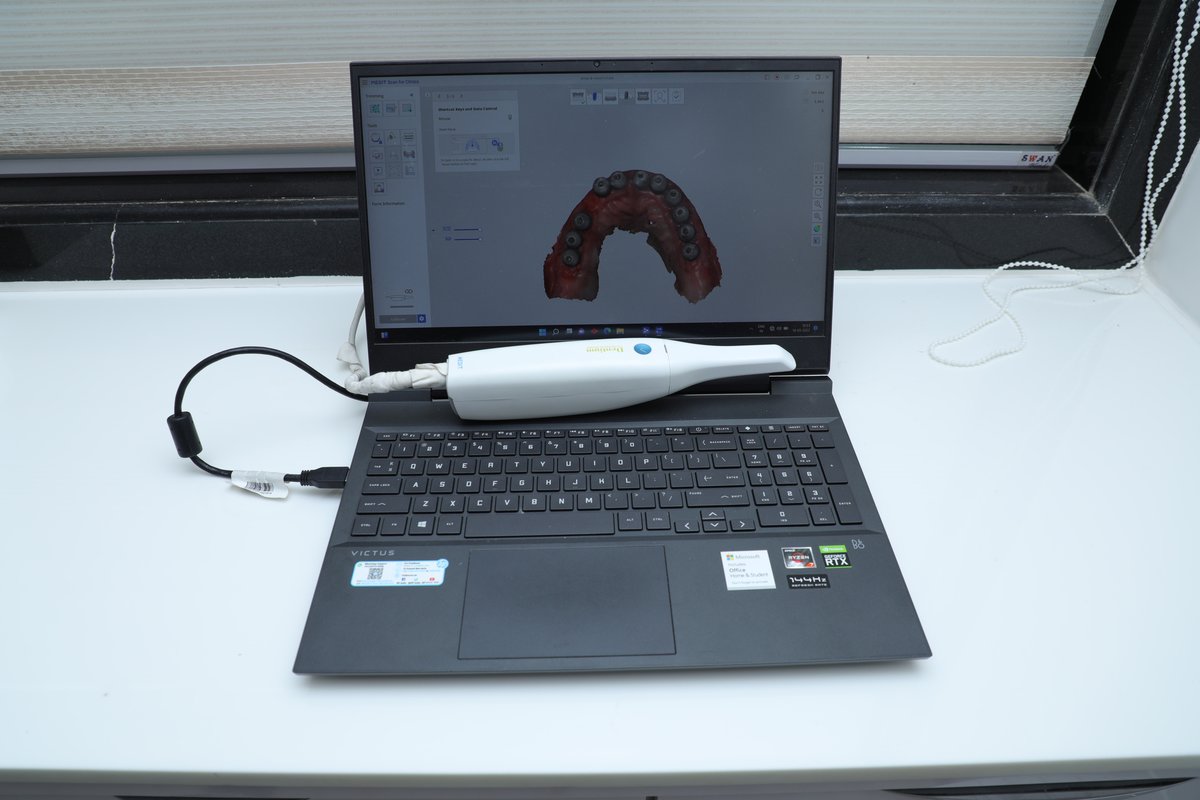

حول عيادة الدكتور ريتشا كوزمودنت لمستحضرات التجميل والأسنان الدكتور سوابنيل باندي والدكتور. ريتشا ميهتا هي المؤسس المشارك للدكتور ريتشا Cosmodent. وقد أكمل كلاهما برامج MDS في زراعة الأسنان ، والتيجان ، والأسنان.. Swapnil عملت أيضا نحو دكتوراه. في زراعة الأسنان. عيادة الأسنان المعتمدة من قبل ISO هي Dr. منشأة Cosmodent في Richa. مع رضا المريض بنسبة 100 ٪ ، نحن نتمسك بمعايير عالمية صارمة في التعقيم والنظافة والرعاية الجيدة وإدارة الممارسة. واحدة من... (عرض المزيد)